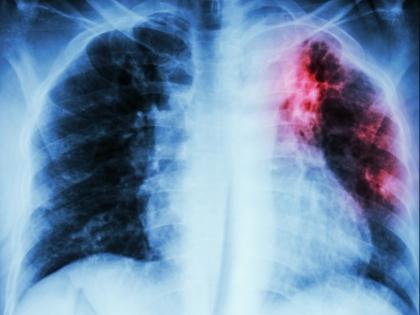

टीबी के बैक्टीरिया का शरीर में प्रवेश फेफड़ों द्वारा होता है लेकिन धीरे-धीरे ये शरीर के इन भागों में भी फैलता है।

तपेदिक, क्षयरोग, एमटीबी, टीबी (ट्यूबरक्लोसिस) एक संक्रामक बीमारी है। यह बीमारी माइकोबैक्टीरियम ट्यूबरक्लोसिस कीटाणु की वजह से होती है। यह कीटाणु हवा के जरिए एक से दूसरे व्यक्ति में पहुंचते हैं। यदि इलाज ठीक से न हो, तो यह रोग जानलेवा हो सकता है। टीबी आम तौर पर फेफड़ों पर हमला करता है लेकिन यह शरीर के किसी भी अंग को प्रभावित कर सकता है। जब टीबी से पीड़ित व्यक्ति खांसता, छींकता या बोलता है, तो उसके साथ संक्रामक ड्रॉपलेट न्यूक्लिआई उत्पन्न होता है जोकि हवा के माध्यम से किसी अन्य व्यक्ति को संक्रमित कर सकता है। आज वर्ल्ड टीबी डे है। इस मौके पर मैक्स हॉस्पिटल में प्रिंसिपल कंसल्टेंट पल्मोनोलॉजी डॉक्टर राजेश गुप्ता आपको बता रहे हैं कि टीबी फेफड़ों के अलावा शरीर के किन-किन अंगों को प्रभावित कर सकता है।

टीबी के बैक्टीरिया का शरीर में प्रवेश फेफड़ों द्वारा होता है। यह बैक्टीरिया शरीर के अन्य अंगों में फ़ैल जाता है। यही वजह है कि आगे चलकर शरीर के किसी भी अंग में टीबी होने का खतरा होता है। यानी आपको दिमाग से लेकर ग्रंथियों, आंख, कान, नाक, लीवर, किडनी, हड्डियों सहित अन्य अंगों में टीबी हो सकता है। खासकर महिलाओं में जनाइटो उरिनरी और जनाइटल ट्रैक्ट टीबी भी बहुत कॉमन होता है। कुल मिलाकर टीबी शरीर के किसी भी हिस्से को प्रभावित कर सकता है।